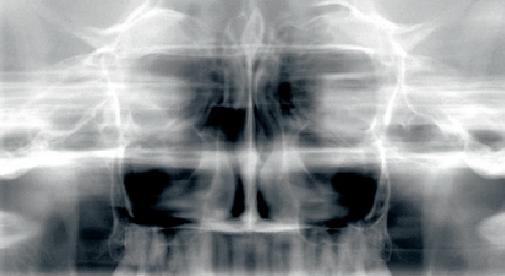

obraz

Obrazowanie zatok szczękowych